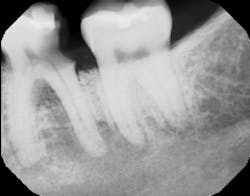

In many cases, removing these lesions in their entirety will increase the risk of canal penetration (figure 2) and subsequent paresthesia (figure 3).

Figure 2: CT scan showing penetration of IAN canal after extraction and socket debridement

Figure 3: Area of resulting paresthesia mapped out clinically